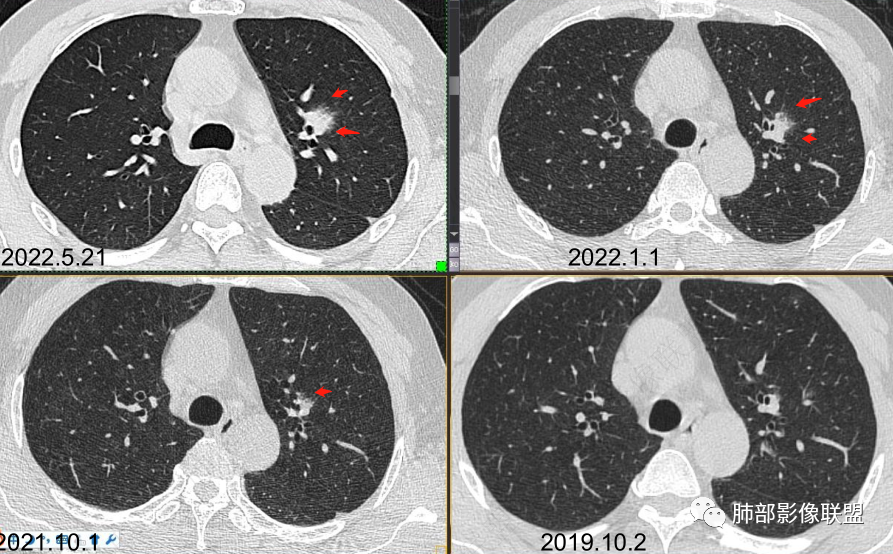

男性,肺结节3年,发现逐渐增大,影像表现,左肺舌段结节,边缘可见磨玻璃密度影,内部走形下舌段支气管变窄,增强呈持续强化,首先考虑肺腺癌,鉴别炎性肉芽肿,真菌/隐球菌。

中老年男性,发现结节,影像表现,左肺上叶结节,实性部分有膨胀性生长,边缘可见磨玻璃影,似清晰似不清晰,病灶与支气管关系密切,部分支气管似狭窄及僵硬,增强病灶强化明显,考虑腺癌(粘液性腺癌)鉴别炎性肉芽肿。

左肺上叶支气管旁结节伴磨玻璃影,磨玻璃边缘略模糊,沿支气管走行,明显不均匀延迟强化,3年逐渐增大,考虑腺癌,鉴别淋巴增殖病变,炎性肉芽肿

中年男性,查体发现,左肺上叶靠近支气管旁实性结节,周围有磨玻璃影,边界清,密度高,明显强化,三年缓慢进展,考虑腺癌,鉴别类癌或炎性肉芽肿。

中老年男性,左肺上叶中轴区实性结节及周围磨玻璃影,磨玻璃边界似清非清,关键点2019.10-2021.10-2022.05结节持续增大,增强后明显强化。考虑恶性结节可能大,腺癌(黏液腺癌)?鉴别炎性结节。

左肺上叶前段实性结节,沿支气管血管束生长,整体形态近三角形,边缘模糊,累及前段气管主支管壁增厚,管腔通畅,前后复查不足两年病灶倍增明显,肿瘤指标阴性,支持炎性肉芽肿,2019年10月2日首诊图,主体结节外周似有小卫星灶分布,需薄层确认,支气管镜肺泡灌洗检查。

361度:

我标示一下,说一下个人的想法

初始病灶应该是这里

病灶朝前、外侧进展

病灶包括两部分

1、实性2、周围GGO

目前看支气管通畅

实性部分强化明显,边缘平直

2、病灶以实性密度为主,前、外侧蔓延,GGO部分边界清楚,部分欠清

支气管未见受明显侵犯,未见阻塞,壁增厚,狭窄或扩张。

软组织+重建;病灶实性部分不是类圆形,密度相对均匀柔和。

肺门区病灶与支气管关系不密切,强化显著、磨玻璃晕等等容易想到的是肺腺癌。而不首先考虑与支气管密切相关恶性肿瘤,如鳞癌、类癌、粘液表皮样癌等等。

1、连续3年观察,病灶逐步增大,符合惰性恶性肿瘤。2、支气管壁增厚,腔内内壁无变化——病灶长轴沿支气管周围蔓延;朝外走,内侧没有,提示病灶间质为主,与支气管无关。

3、GGO长期存在,朝外蔓延,支持恶性特点。

支持淋巴瘤的关键点:1、间质为主;2、与支气管无关;3、边缘GGO的长期存在支持恶性

因为与支气管无关不支持腺癌,还是要警惕淋巴瘤。